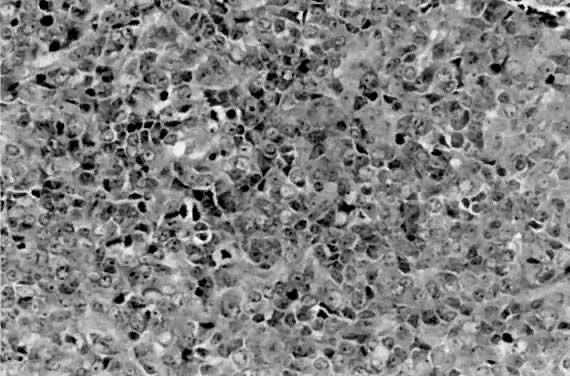

Tumors lacking definitive glandular or squamous differentiation are termed undifferentiated carcinomas. This group is often divided into large and small cell categories.54 Small cell carcinomas range histologically from diffuse sheets of poorly differentiated cells (Fig. 16), similar to small cell carcinomas of other locations, to patterns simulating carcinoid tumors.55 Reactivity with neuroendocrine antibodies is not uncommon in the small cell group.54,56 Also described in the literature are undifferentiated carcinomas with multinucleated giant cells,57 occasionally resembling osteoclast-like giant cells. The prognosis is comparable to a grade 3 endometrial carcinoma, regardless of small or large cell morphology.

Fig. 16. Small cell carcinoma is characterized by sheets of round to oval cells with granular chromatin and often dot-like nucleoli. The mitotic rate is quite high in these clinically aggressive lesions.